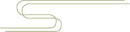

解剖

远端腓骨表面覆盖着较厚的纤维软骨(纤维软骨脊),使得骨-纤维管深度增加 2 ~ 4 mm,且形状更适于容纳腓骨肌腱,从而促进应力分散。研究发现腓骨肌沟可呈现凹陷、平坦、凸出三种形态。